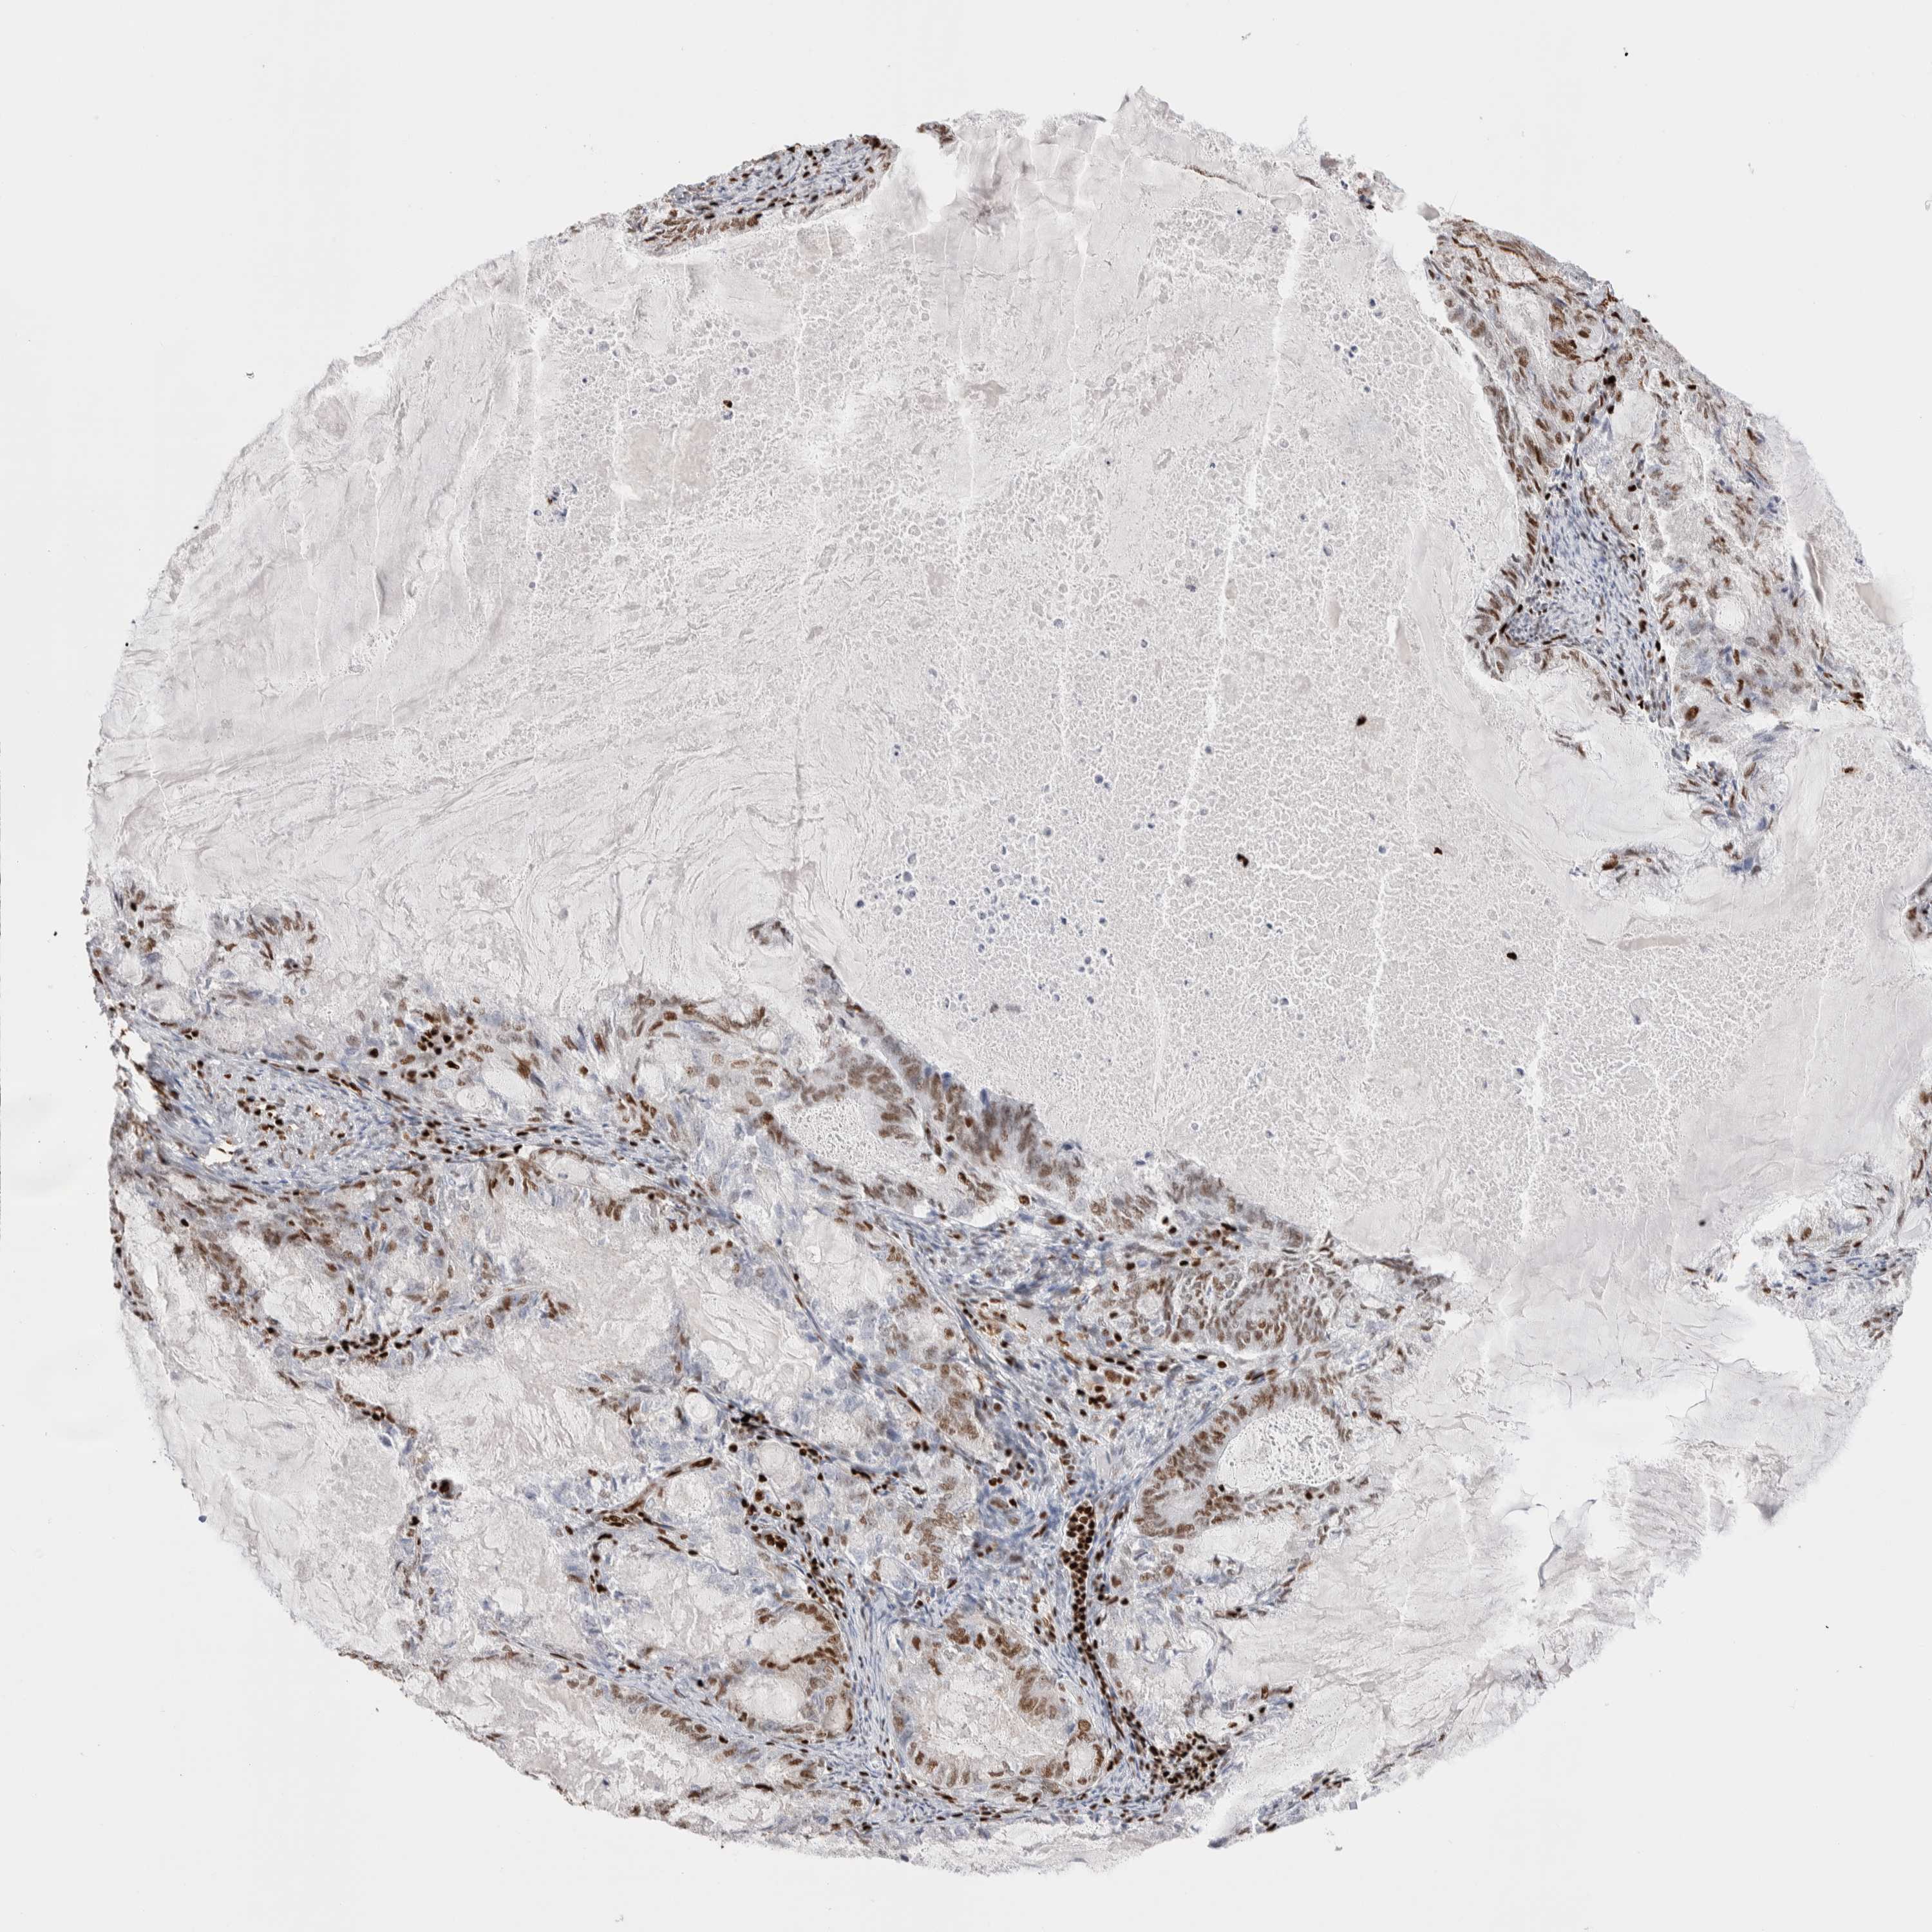

ENDOMETRIAL CANCER - Protein expressioni

A mouse-over function shows sample information and annotation data. Click on an image to view it in a full screen mode. Samples can be filtered based on level of antibody staining by selecting one or several of the following categories: high, medium, low and not detected. The assay and annotation is described here.

Note that samples used for immunohistochemistry by the Human Protein Atlas do not correspond to samples in the TCGA dataset.

Antibody stainingi

Antibody staining in the annotated cell types in the current human tissue is reported as not detected, low, medium, or high, based on conventional immunohistochemistry profiling in selected tissues. This score is based on the combination of the staining intensity and fraction of stained cells.

Each image is clickable and will lead to virtual microscopy that enables deeper exploration of all samples and also displays staining intensity scores, fraction scores and subcellular localization as well as patient and tissue information for each sample.

Antibody HPA022961

Antibody HPA024457

Staining

High

Medium

Low

Not detected

Intensity

Strong

Moderate

Weak

Negative

Quantity

>75%

75%-25%

<25%

None

Location

Nuclear

Cytoplasmic/membranous

Cytoplasmic/membranous,nuclear

Adenocarcinoma, NOS

Adenoma, NOS